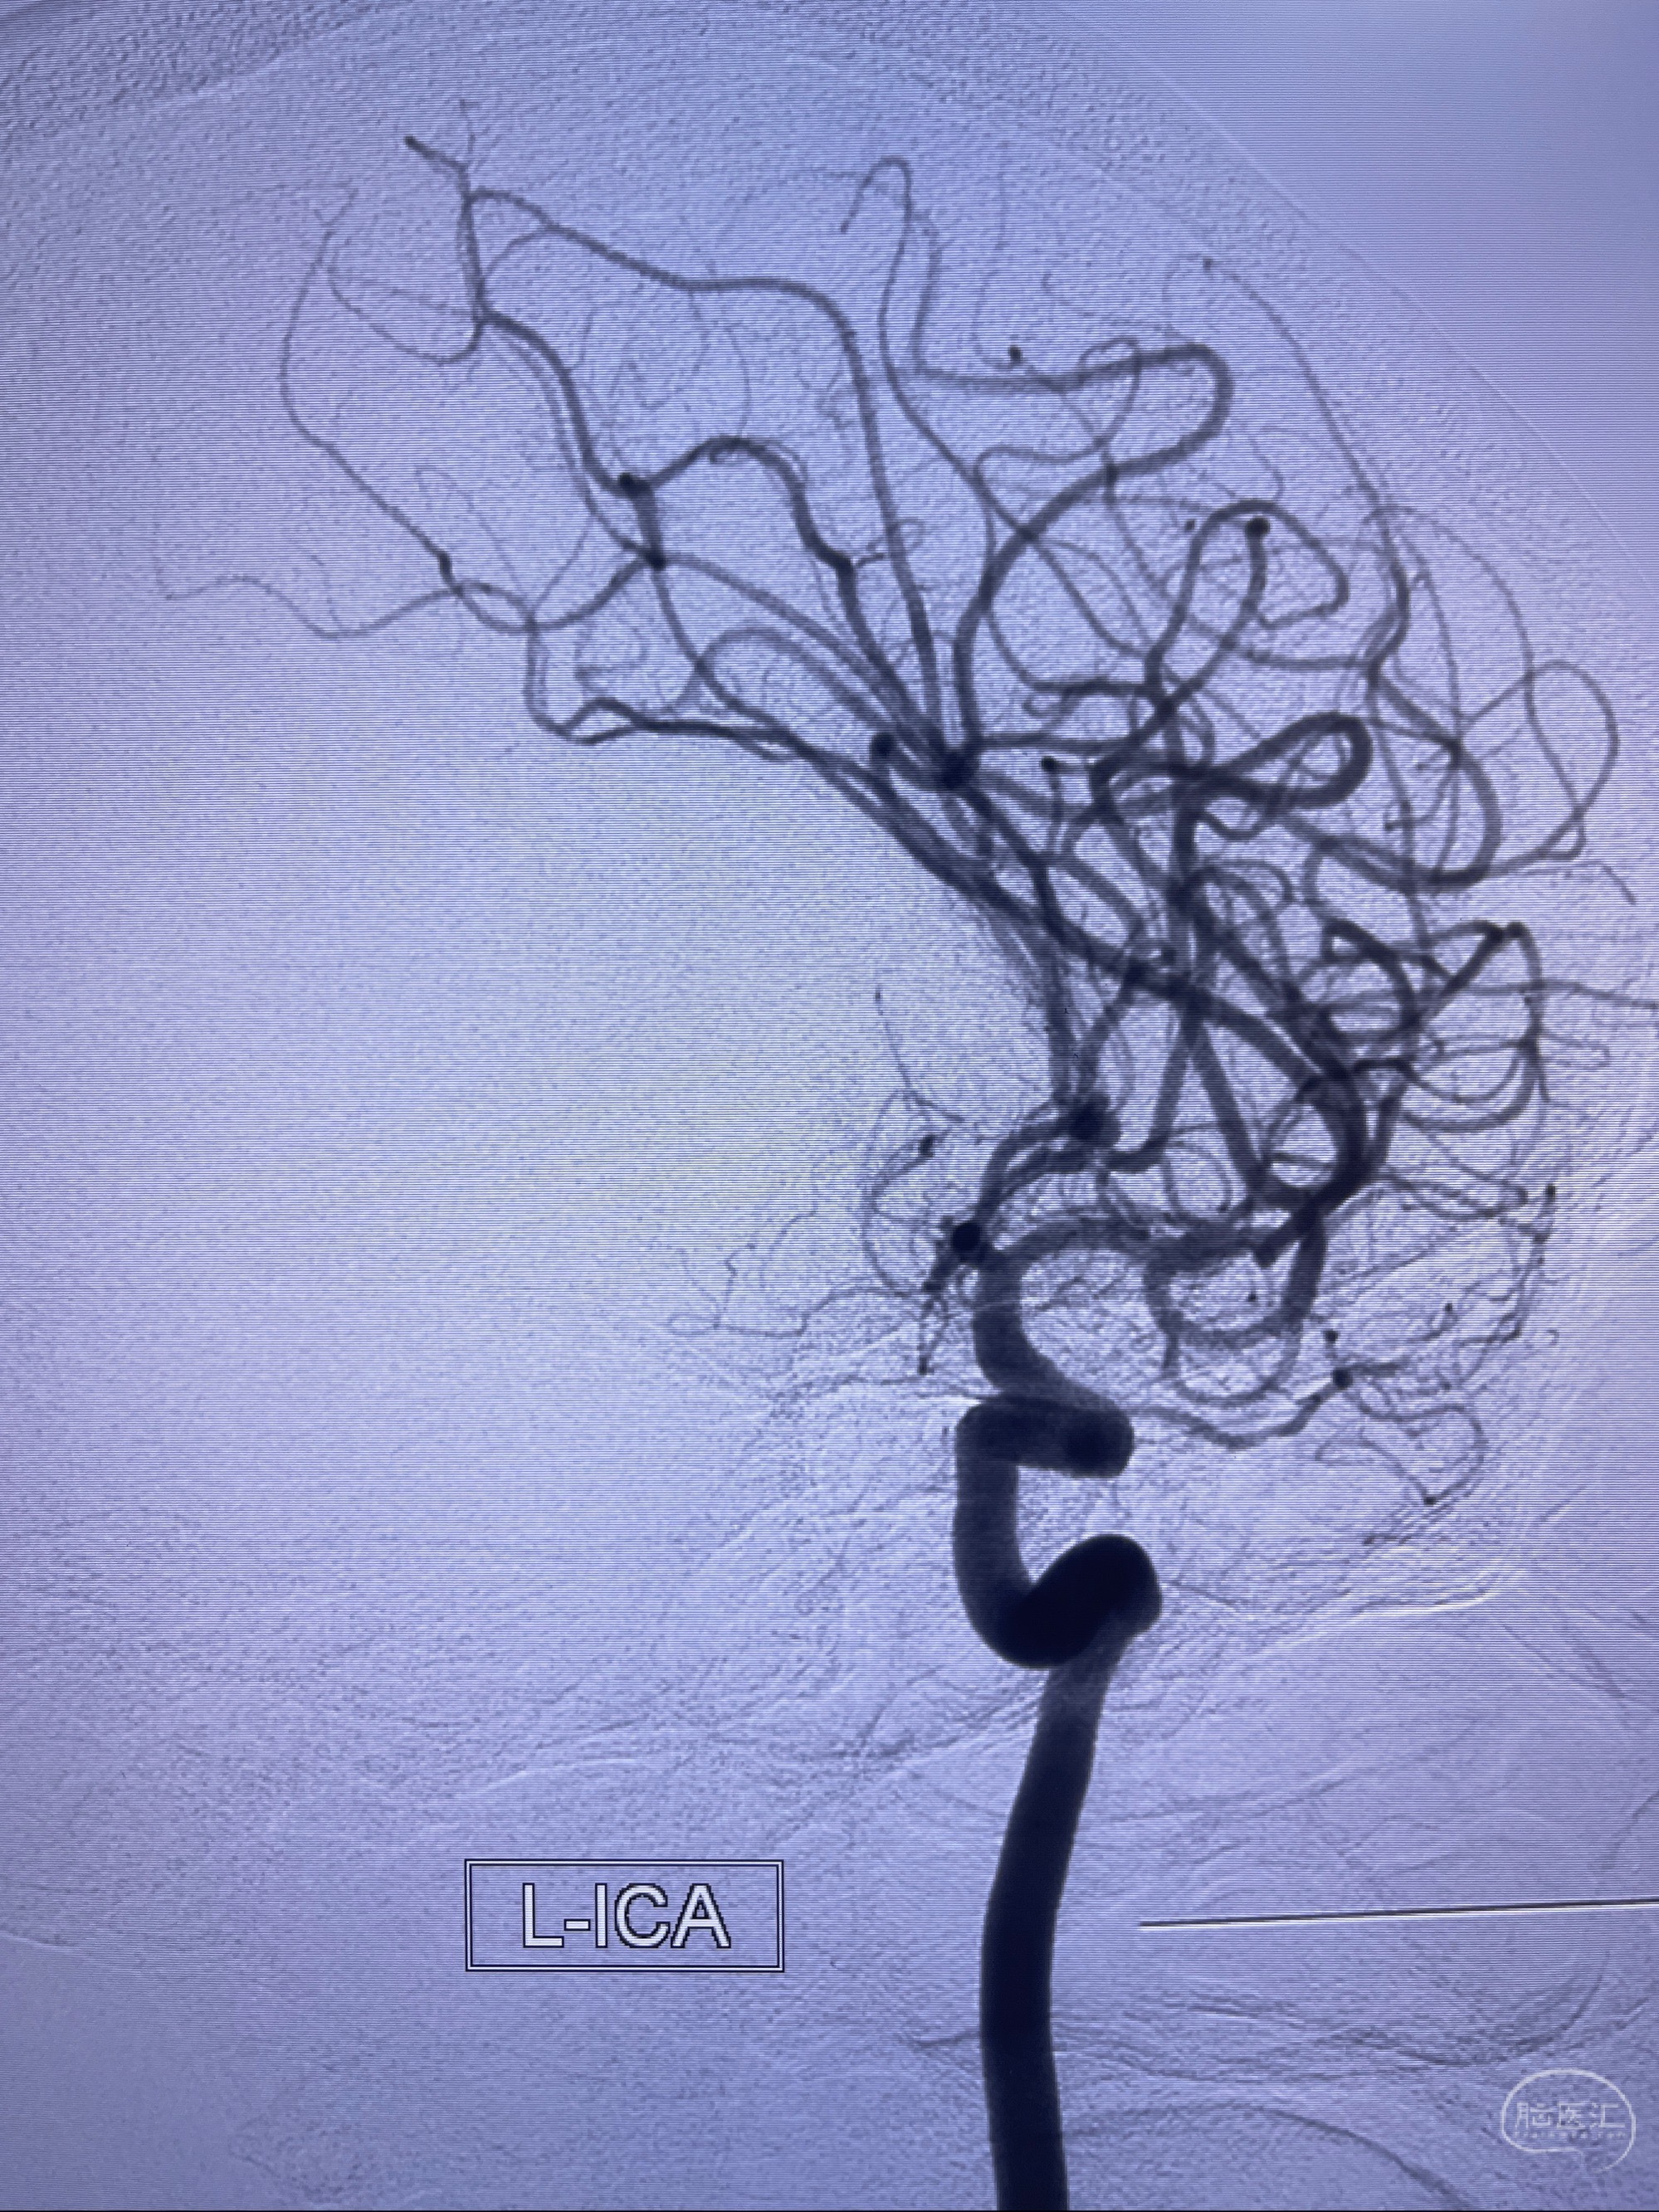

1.左侧大脑前动脉远侧段(A2-A5)动脉瘤

2023-08-23DSA:左侧前交通动脉瘤,左侧A3/4交界处多发动脉瘤